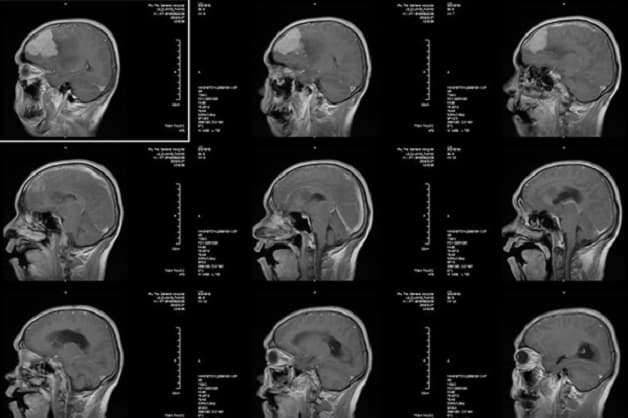

Với những trường hợp trên, kết quả chụp CT scan sọ não sẽ cung cấp hình ảnh rõ nét, đặc biệt có độ phân giải phần mềm vùng não và không gian tốt. Từ đó bác sĩ dễ dàng hơn trong việc chẩn đoán tình trạng bệnh lý mà người bệnh đang gặp phải.

Những người gặp chấn thương sọ não có thể được chỉ định thực hiện chụp CT scan

Chụp CT scan vùng sọ não là kỹ thuật chẩn đoán hình ảnh hiệu quả